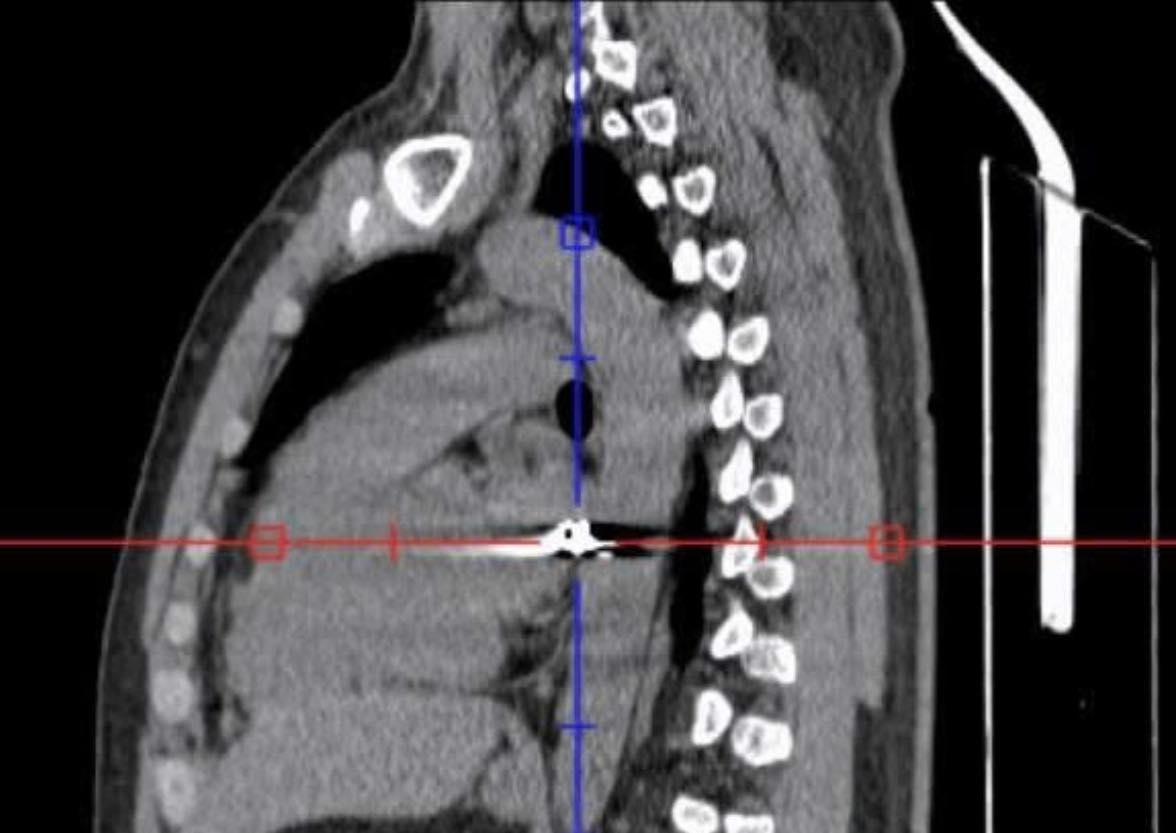

Bệnh nhân P.V.H (32 tuổi, ngụ xã Thanh Sơn, tỉnh Đồng Nai) nhập viện vào khoảng 11 giờ ngày 20/4 trong tình trạng nguy kịch. Qua thăm khám ban đầu, các bác sĩ xác định viên đạn đi theo đường phức tạp từ vùng lưng phải xuyên qua lồng ngực sang bên trái – khu vực tập trung nhiều cơ quan trọng yếu như tim, phổi và các mạch máu lớn, đe dọa trực tiếp đến tính mạng người bệnh.

Sau hơn 4 giờ phẫu thuật căng thẳng, các bác sĩ đã kiểm soát được tổn thương, đồng thời gắp thành công một đầu đạn có kích thước khoảng 0,3 x 0,5 cm ra khỏi cơ thể bệnh nhân. Đây là yếu tố then chốt giúp hạn chế nguy cơ nhiễm trùng, chảy máu tái phát và các biến chứng nặng nề về sau.